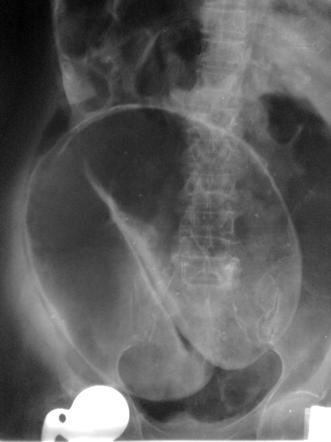

Volvulus:

Sigmoid is most common

Huge distention in bed ridden elderly w/ no previous surgeries.

Xray: coffee bean

Unstable: Hartman’s procedure

Stable: Colonoscopy & elective resection same admission

Cecal volvulus: Rt hemicolectomy, no deflation

Some centers: PEC tube (see pix)